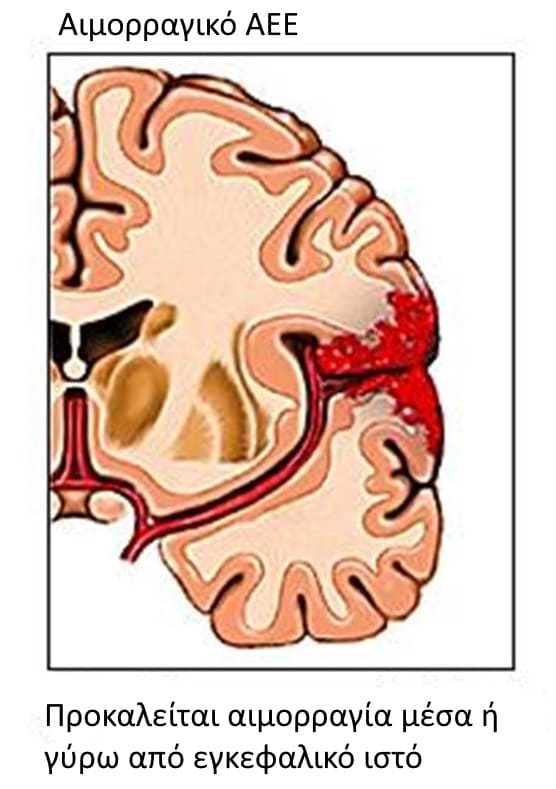

2. Αιμορραγικού τύπου

Τα αιμορραγικά αγγειακά εγκεφαλικά επεισόδια οφείλονται στη ρήξη ενός εγκεφαλικού αγγείου με συνέπεια την πρόκληση ενδοεγκεφαλικής ή υπαραχνοειδούς αιμορραγίας. Οι παθολογικές καταστάσεις που προδιαθέτουν σε αιμορραγικά αγγειακά εγκεφαλικά επεισόδια στο σκύλο είναι :

Ρήξη αγγείου και πρόκληση ενδοεγκεφαλικής ή υπαραχνοειδούςαιμορραγίας